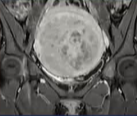

影像学检查:盆腔磁共振(MRI)平扫+增强是金标准。用于明确肌瘤的大小、数量、位置(如浆膜下、肌壁间、粘膜下)、血供情况、与内膜的关系,并排除恶性可能。这是决定治疗方案的关键

实时监控:医生通过实时影像(MR或US)规划治疗范围,逐点进行消融。治疗中医生会与患者沟通,如下腹部发热、酸胀等感觉均属正常。